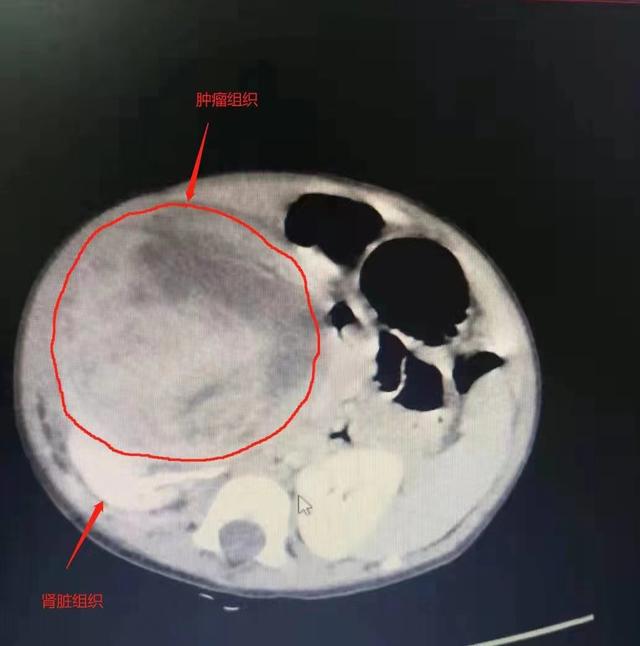

两个多月前,来自湖北荆州的10个月大的小宇持续低烧。我以为这是小孩子常见的发烧和感冒。然而,经过几周的治疗,小宇的症状一点也没有缓解。上腹部CT显示右肾有巨大占位性病变。一个直径10厘米的异物,看起来像“第三肾”,与右肾紧紧包裹在一起。

武汉市人民医院泌尿外科三科主任樊城教授全面检查了临床症状和影像学表现。第三个肾高度怀疑是肾母细胞瘤。